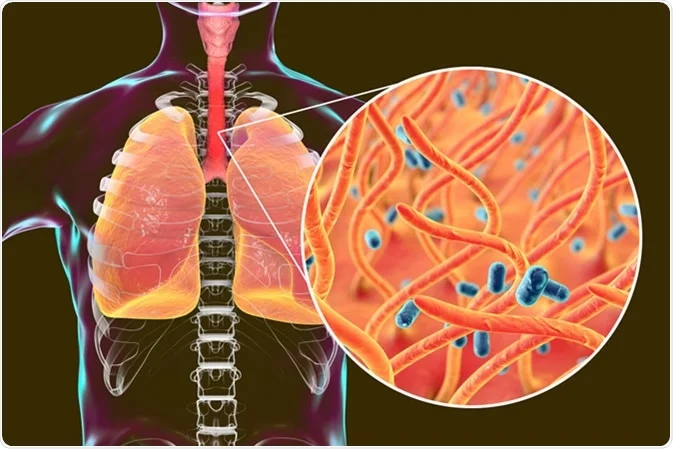

Whooping cough, also known as pertussis, is a highly contagious respiratory infection caused by the bacterium Bordetella pertussis. It is characterized by severe coughing fits followed by a distinctive “whooping” sound as the individual gasps for air.

The primary causative agent of whooping cough is Bordetella pertussis, a Gram-negative bacterium. Another species, Bordetella parapertussis, can also cause a similar illness, albeit typically with milder symptoms.